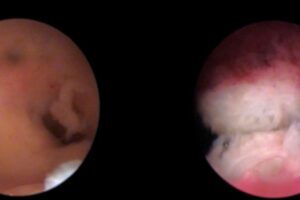

Unos por salud, otros por la economía y una gran parte por la persecución de la sociedad al “enfermo” del tabaco. Ahora debemos añadir otro motivo para dejar de fumar, “lograr un embarazo”

Si eres fumadora y quieres llegar al embarazo, ¿no crees que es lógico que la madre naturaleza no te lo ponga fácil si te metes más de 4000 compuestos tóxicos a diario entre pecho y espalda?

Para formar a un bebé, sus células no necesitan al monóxido de carbono, el polonio, el cianuro, la nicotina, el plomo ni el alquitrán. Más bien al contrario, estás envenenando sus células de forma silenciosa. Algunos más radicales podrían considerar este acto desde un “homicidio involuntario” a un “asesinato premeditado”. Nosotros no lo seremos tanto.

Tanto el hombre como la mujer fumadora, recibe grandes cantidades de cadmio, un metal tóxico que inhibe al zinc, el mineral fertilizante tanto del hombre como de la mujer. El cadmio no desaparece del cuerpo una vez dejamos de fumar. Se tiene que llevar a cabo varios procesos para eliminarlo aumentando la ingesta de antioxidantes, tanto a través de frutas y vegetales crudos como a través de suplementos de vitamina C, vitamina E, ácido lipoico y selenio.

Más preocupante es que el cadmio puede concentrarse en la placenta una vez te encuentres embarazada. Incluso si eres fumadora pasiva.